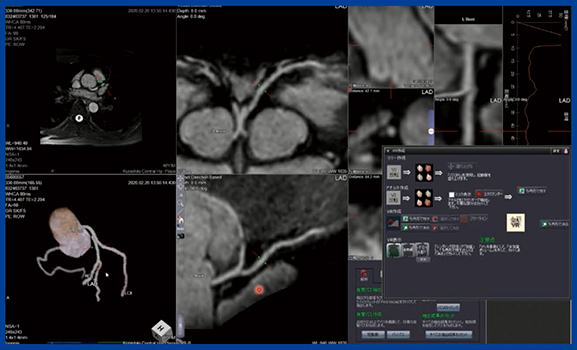

当院では,2017年から心臓MRI検査を含めた心臓ドックを開設し,年間120〜130件行っている。1.5T装置でwhole heart coronary arteryを撮像し,Ziostation2の「MR冠動脈解析2」を用いて,自動で冠動脈を抽出してVRおよびCPRの作成をスピーディに行っている(図1)。

図1 MR冠動脈解析2によるMRCAの自動解析